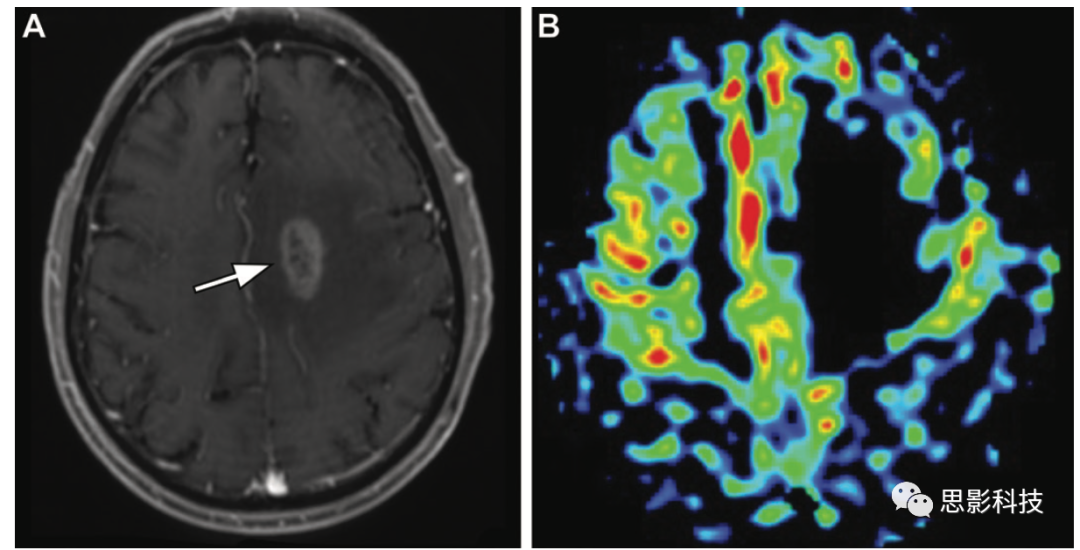

癲癇 ASL MRI可以幫助評(píng)估癲癇,其結(jié)果已被證明與SPECTPET研究結(jié)果一致。ASL MRI可以識(shí)別潛在病灶,有助于鑒別診斷。癲癇發(fā)作的機(jī)制、時(shí)機(jī)和慢性化等因素可能會(huì)影響ASL成像。因此,關(guān)于患者的臨床病史和成像時(shí)表現(xiàn)是至關(guān)重要的。在發(fā)作期和急性發(fā)作間歇期,由于神經(jīng)元活動(dòng)增加,活躍的致癇區(qū)顯示出高血流量(19)。在慢性發(fā)作間歇期,由于活躍度和功能降低以及不成比例的萎縮,致癇區(qū)可能表現(xiàn)出低血流量

19 一名54歲男性癲癇發(fā)作30分鐘后的早期發(fā)作后狀態(tài)。(A,B)冠狀面FLAIR(A)和軸位高分辨率增強(qiáng)T1加權(quán)(B)顯示左側(cè)海馬和鉤回(箭頭)呈高信號(hào),略有強(qiáng)化。(C)ASL表明相關(guān)區(qū)域(箭頭)的高灌注,有助于識(shí)別潛在致癇灶,并隨著時(shí)間的推移有不同的表現(xiàn)。

偏頭痛 ASL可以用于了解偏頭痛的機(jī)制和病理生理學(xué)。偏頭痛可能與腦血管失調(diào)有關(guān),ASL異常。在偏頭痛先兆中,與癥狀相對(duì)應(yīng)的皮質(zhì)表現(xiàn)為腦血流量降低。在偏頭痛急性期,受影響的皮質(zhì)可能表現(xiàn)出CBF增加(20)。

20 患者為31歲男性,偏頭痛持續(xù)約2天,主要發(fā)生在左側(cè)枕葉,并伴有暗點(diǎn)和半球面部感覺異常。

(A)軸位FLAIR圖像顯示正常。

(B)ASL MRI顯示左側(cè)枕葉(箭頭)呈現(xiàn)局部過度灌注。繼發(fā)于偏頭痛先兆的可能高灌注應(yīng)列入診斷的第一假設(shè)。